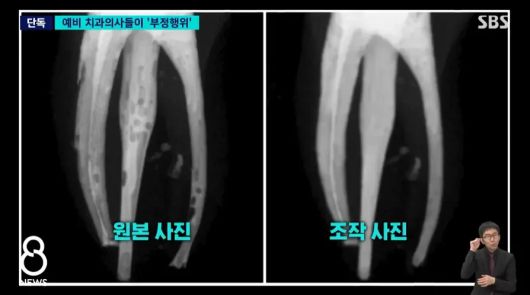

학생들은 교수진에 신경치료 뒤 깨끗한 치아 뿌리를 담은 엑스레이 사진을 냈다. 그러나 실제 원본 사진은 달랐다. 치아 뿌리는 신경치료 과정에서 충전재를 꼼꼼히 채워 넣지 않아 여러 군데에 구멍이 뻥뻥 뚫린 듯한 모습이었다. 교수진에 제출된 사진은 학생들이 포토샵 프로그램을 이용해 기포를 말끔히 지워 마치 치료가 잘 된 것처럼 조작한 것이었다.